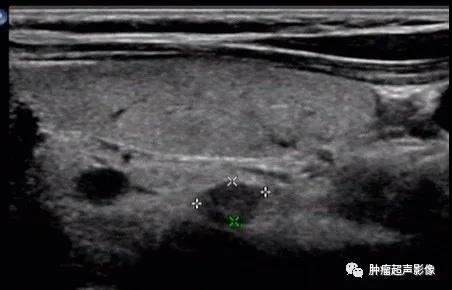

慢性肾脏疾病,血PTH升高,左右各见两个(共四个)增大的甲状旁腺腺体,呈边界清的低回声,与甲状腺分界清晰。